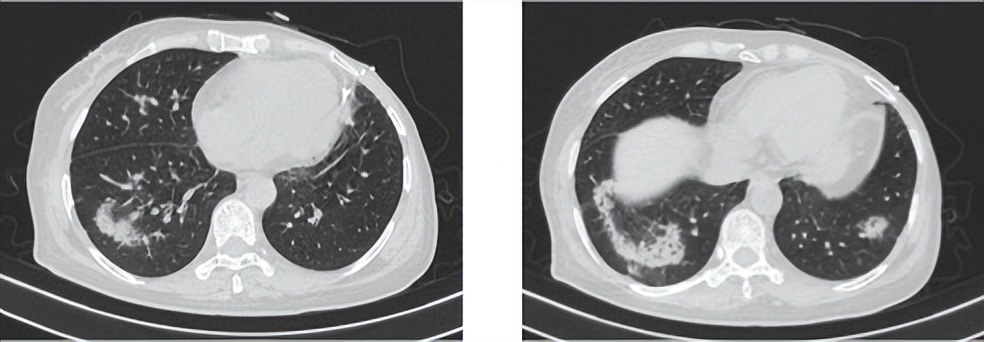

执行情况及治疗结局:

行抗生素激素治疗后患者症状明显缓解,影像学提示间质性改变较前明显改善(图1-6),2021.11.23-2022.04行UTD1化疗6周期,疗效评价PR(图1-7,1-8)。

图1-6

图1-7

图1-8